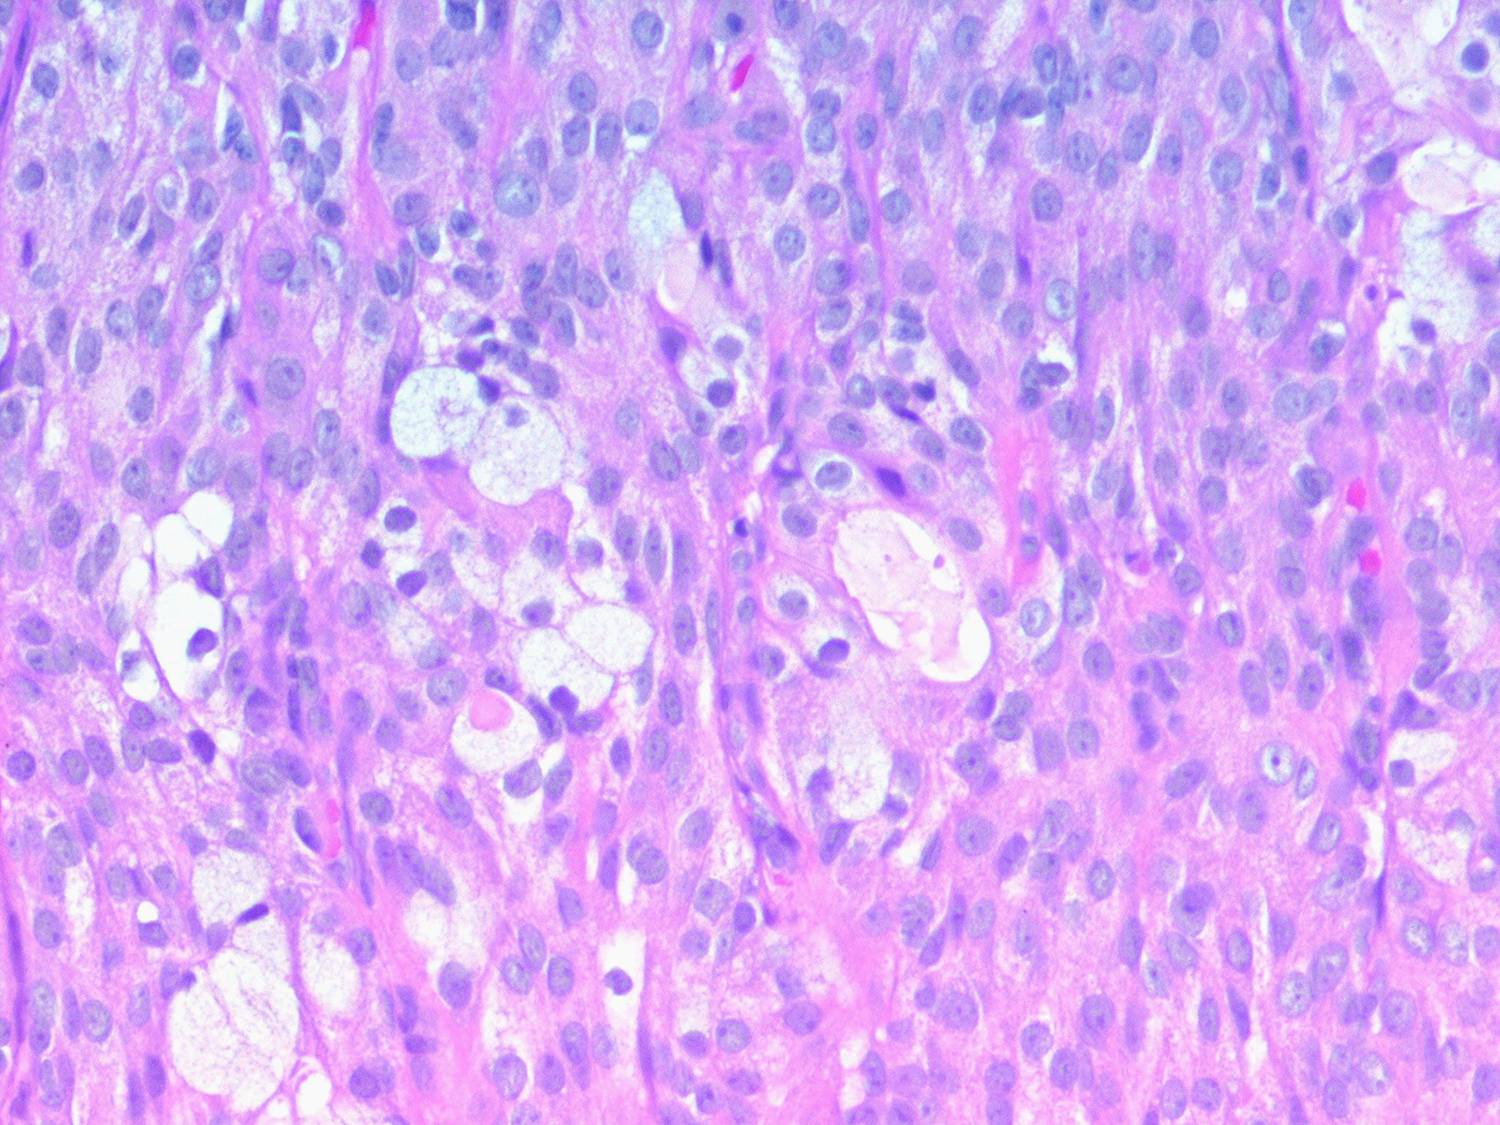

Mucoepidermoid carcinoma =الكارسينوما المخاطية البشروانية